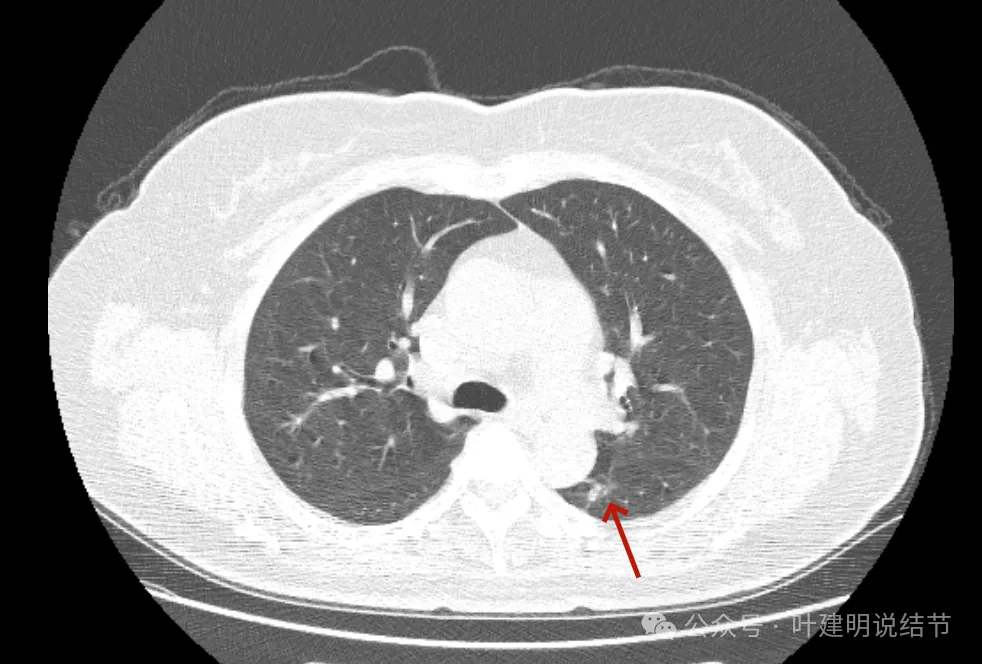

最后看2024年复查的影像:

病灶出现,密度不纯,毛刺细长。

轮廓稍显模糊,密度不均,毛刺偏长。

病灶膨胀感较之前明显;与主动脉壁之间缝隙不太明显了。

实性成分似乎较前增多,胸膜略有牵拉。

膨胀性较前明显,基本实性。

与主动脉壁贴得紧了,但褐色所指处边缘还是较为平直。

与主动脉壁之间紧贴了,对侧出现了细毛刺,整体基本都是实性密度了。

实性成分占比增加,邻近结构受压,边缘毛刺出现。

表面不平,密度高,与主动脉间隙消失。

现在较2年前有进展,显示了更多的恶性影像特征,整体密度也增加,膨胀性也明显起来,并对邻近结构有压迫,表面不平毛糙。持续存在的实性为主的结节随访进展,并显示出更多恶性特征,那就得高度怀疑恶性,而且不宜再随访了。